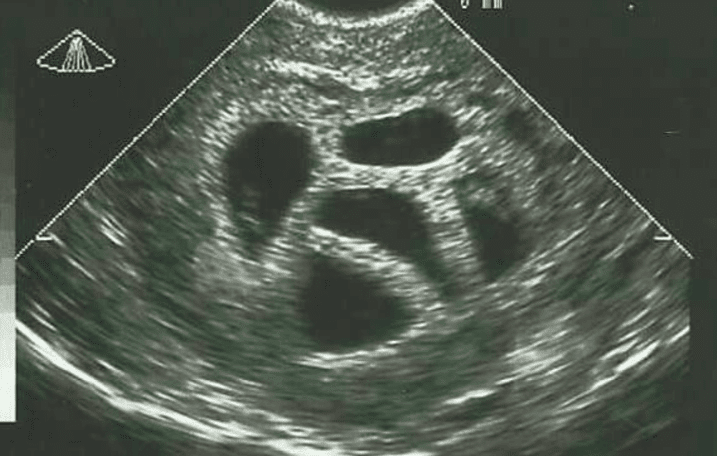

Er is iets bijzonders te vertellen over een moeder genaamd Susan, die twintig jaar geleden voor een moeilijke keuze stond. Op 28-jarige leeftijd ontdekte ze dat ze in verwachting was van een vijfling. De artsen die haar bijstonden, adviseerden haar om voor een ‘selectieve abortus’ te kiezen. Dit betekent dat je één of meerdere embryo’s of foetussen kunt laten verwijderen om de overlevingskansen van de anderen te verbeteren. Maar Susan vond dit geen optie en legde het advies naast zich neer.